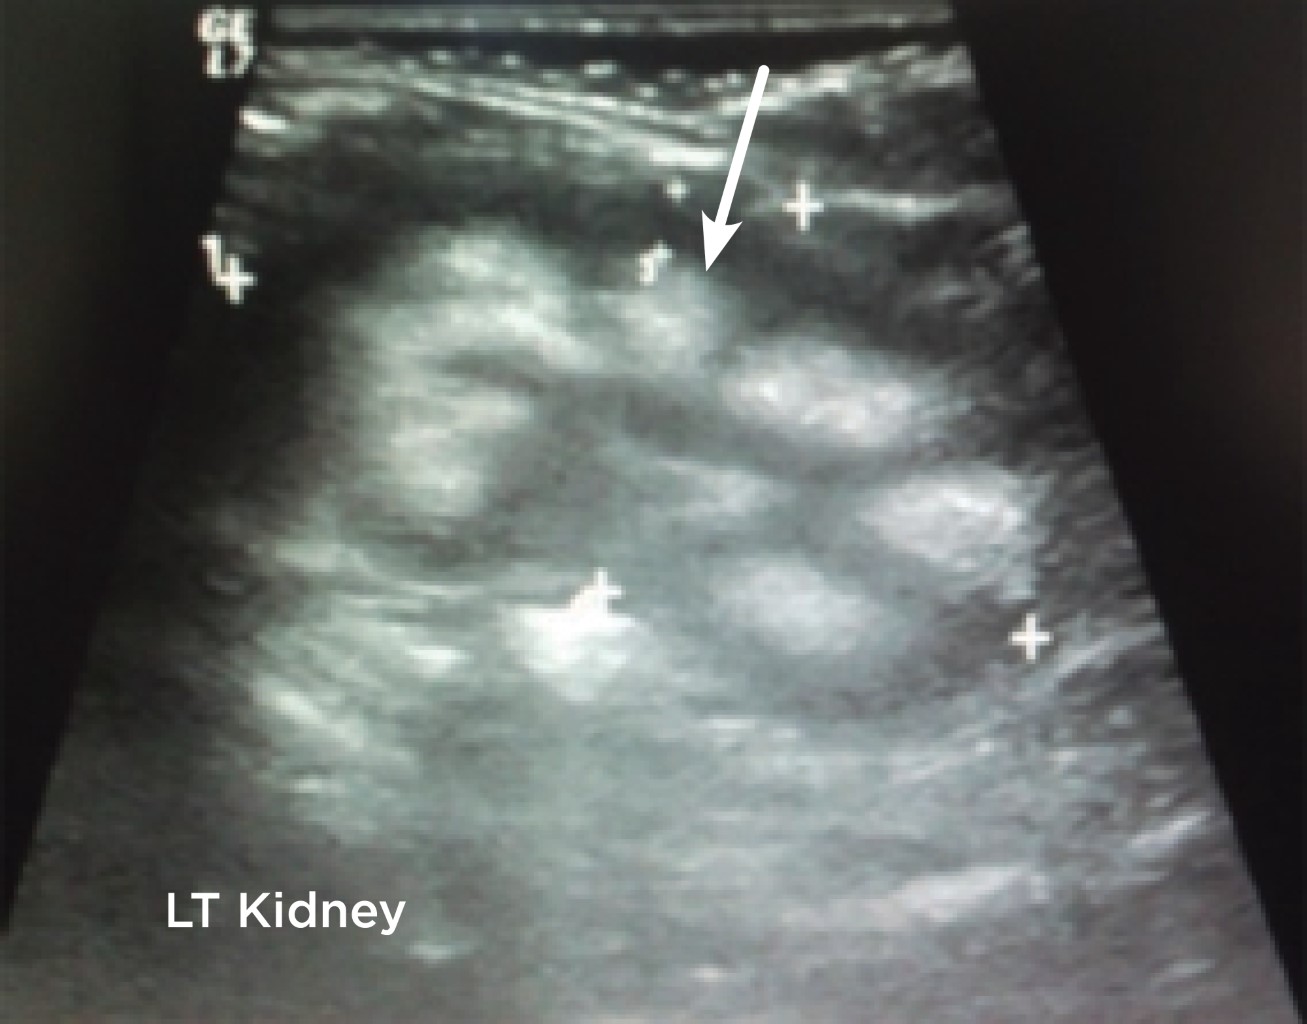

Durante su estancia hospitalaria se trata de forma satisfactoria la falta de volumen; sin embargo, persiste con acidosis metabólica hiperclorémica, por lo que ameritó infusión de bicarbonato, al corregir la acidosis se suspende y nuevamente presenta acidemia. Se consideró de forma inicial enfermedad tubular y en un interrogatorio dirigido a la madre refirió los siguientes antecedentes: polihidramnios, debilidad para la deglución, apetito por el agua, poliuria, rechazo del seno materno sin incremento del peso y de la talla. Por lo tanto, el aporte de bicarbonato se dejó permanentemente. En la consulta de nefrología se solicita ultrasonido renal para valorar la presencia de alguna afección coadyuvante y se observa nefrocalcinosis, confirmando el diagnóstico de acidosis tubular renal distal (Figuras 1 y 2). Los resultados de los exámenes de laboratorio al ingreso se muestran en la Tabla 3.

Figura 1

Figura 2